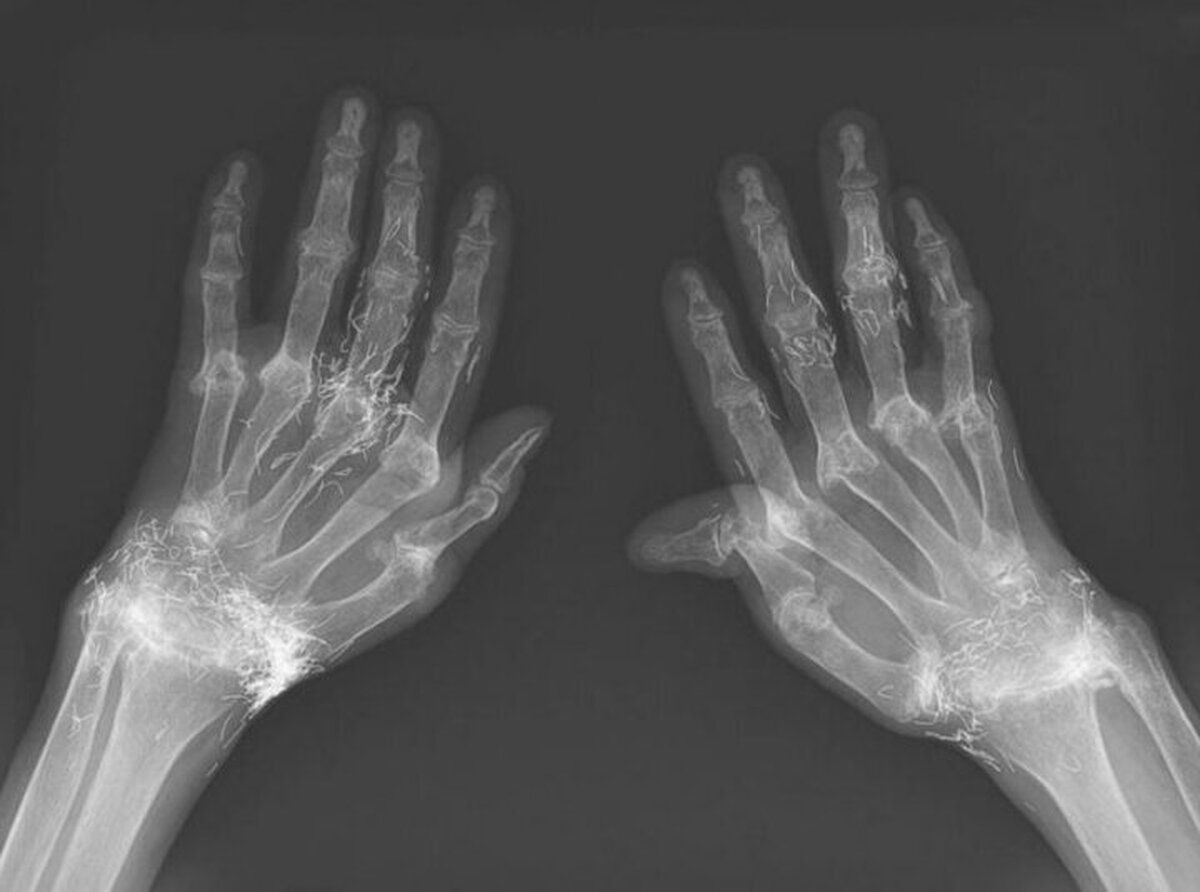

در یک مورد نادر پزشکی در کره جنوبی، پزشکان هنگام درمان درد و خشکی شدید زانوهای زنی که به آرتروز مبتلا بود، متوجه وجود صدها رشته طلای خالص در بافت‌های اطراف زانوهای او و البته دست‌هایش شدند.

در جلسات هفتگی طب سوزنی با نخ طلا،‌ رشته‌هایی بسیار ریز در بافت‌های اطراف زانوهای او قرار داده می‌شد. البته از آنجایی‌که دست‌های این بیمار هم درد می‌کرد، درمانگر او برای دست‌هایش هم این نوع درمان را انجام داد.

اما این روش هم نه‌تنها دردی از این زن دوا نکرد، بلکه زانودرد او را هم شدت بخشید. درنهایت او مجبور شد دوباره به بیمارستان مراجعه کند و پزشکان هنگام تصویربرداری از زانوها و دست‌های او متوجه صدها رشته‌ ریز و نازک از طلا در بافت‌های اطراف زانو و دست‌های این زن شدند.

طب سوزنی با رشته‌های طلا در برخی از کشورهای آسیایی، به‌ویژه میان سالمندان، رایج است اما پزشکان هشدار دادند این روش هیچ پشتوانه علمی ندارد و حتی ممکن است موجب عوارض خطرناکی چون ایجاد کیست، جابه‌جایی نخ‌ها در بدن، آسیب به بافت‌ها و حتی اشکال در انجام تصویربرداری MRI شود.